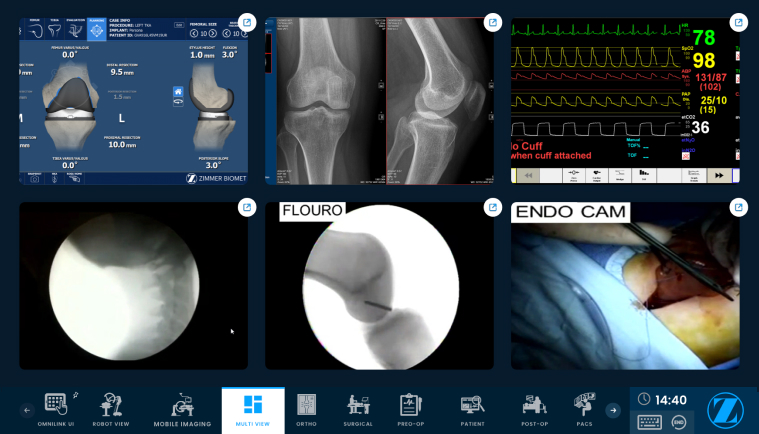

The result was a dynamic, intelligent OR solution—powered by AI-driven automation, computer vision, speech recognition, and interoperability standards—that not only redefined hospital workflows but also reinforced the client’s leadership in intelligent surgical systems. The transformation accelerated surgical outcomes, reduced manual interventions, and positioned the client’s portfolio as future-ready for global deployment.

We made the OR self-aware with AI-powered computer vision, automating instruments and events while delivering real-time insights, setting the foundation for intelligent workflows.

Building on this foundation, we created a cross-platform, interoperable OR system with live streaming and adaptive workflows, enabling real-time monitoring and global collaboration.